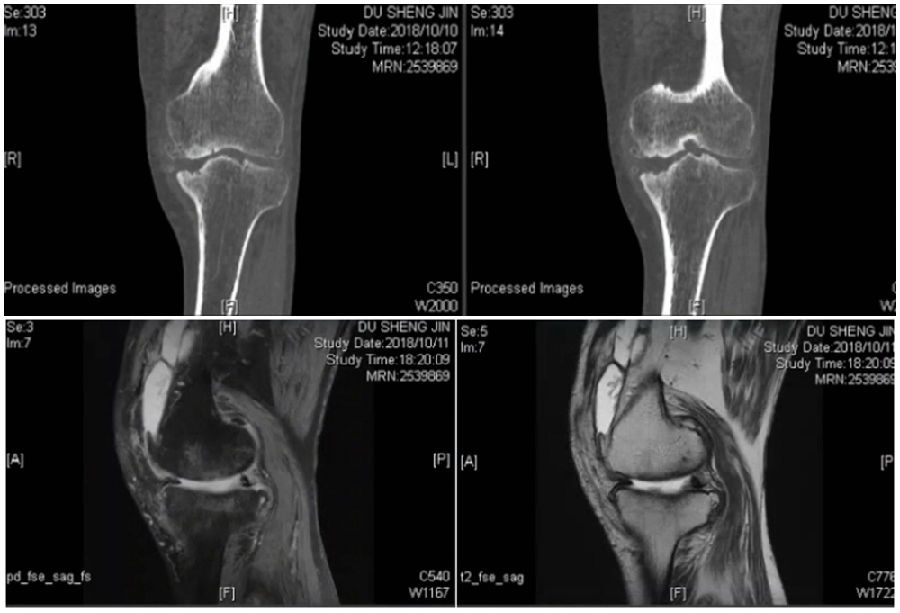

术前

术前影像资料

术前MRI

术前规划:

①关节内截骨,内外侧平台平行。

关节内截骨

②再次确定下肢力线。

确定力线

③关节外截骨。

关节外截骨